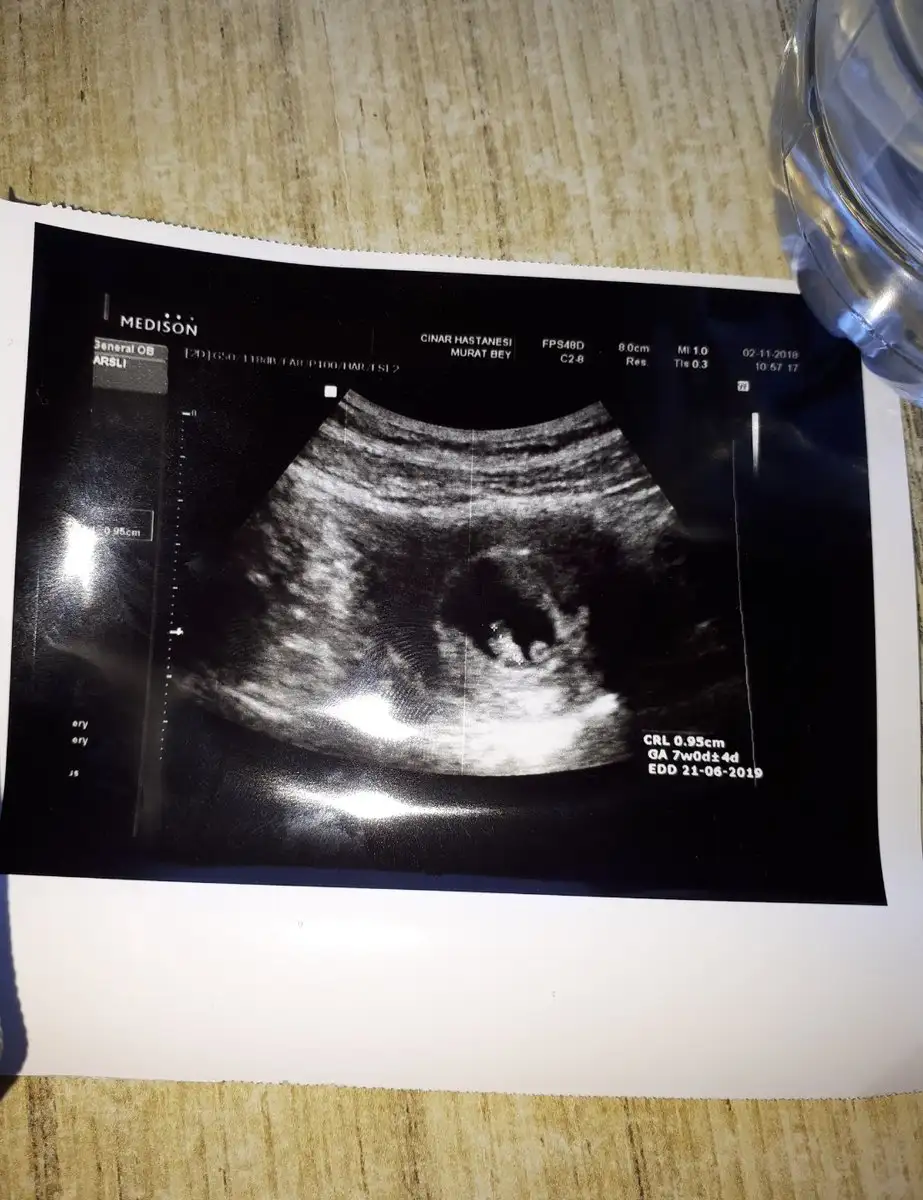

merhaba arkadaslar ultrason görüntüsünü yorumlayabilecek tecrübeli anne ve adayları var mı acaba:) benim hesabıma göre 7+1 resimde 7w0d+4d yaziyo bu nedemek? Kalp atışlarını karından ultrasonla duydum binlerce şükür ve hiç bir belirtim hala yok

hayırlı olsun inşallah sağlıkla ilerler hamileliğiniz. Ultrason ölçümüne göre 7 hafta 4 günlük çıkmış. Ancak gebeliğiniz boyunca bu ölçüm sürekli değişecek zaten. Normal haftanızla ultrason ölçümü arasında belli bir haftaya kadar oynamayı normal kabul ediyor doktorlar.